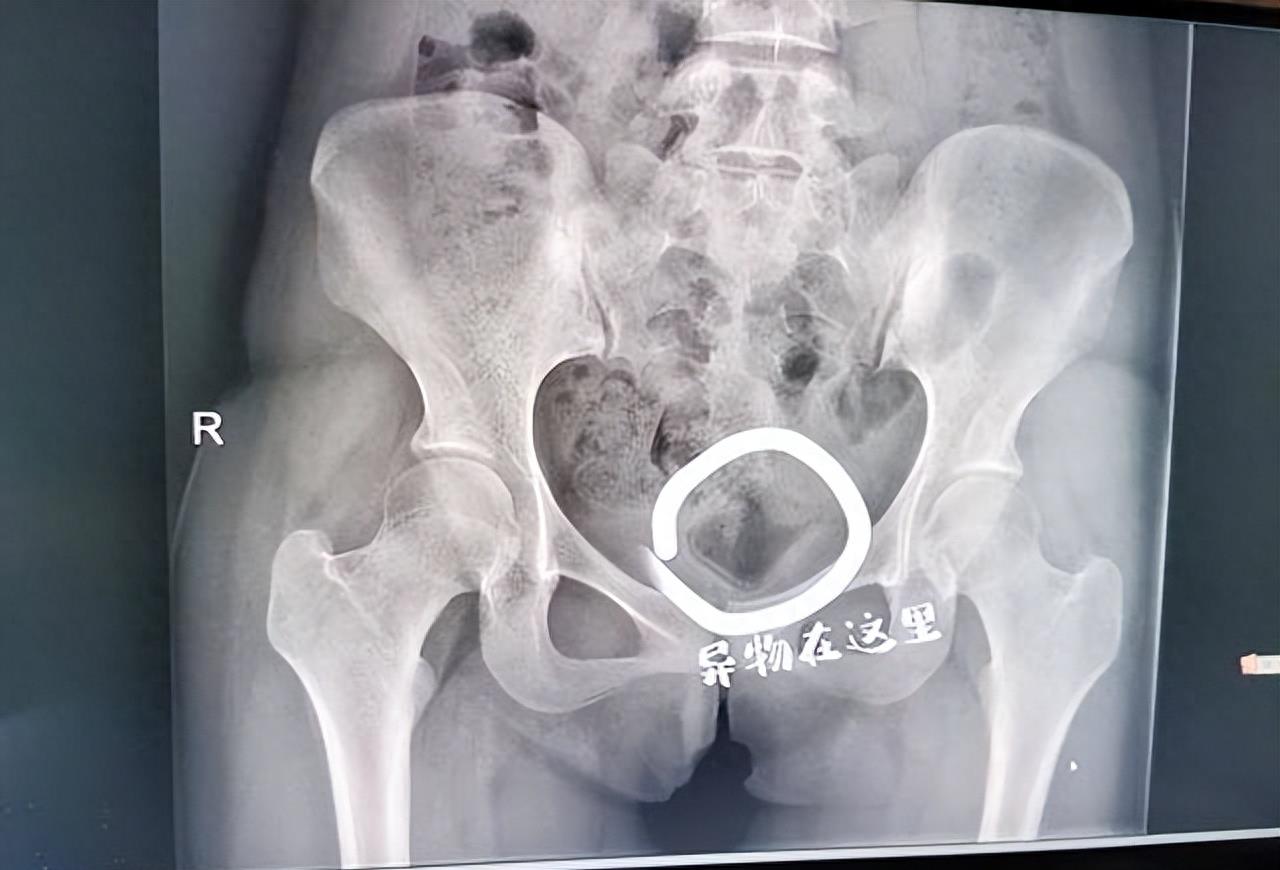

在医院,经过检查,医生确定小杨体内存在异物,并且炎症反应已经显著。医生提醒小杨,将异物长时间放置在体内不仅可能引发感染,还可能对生育功能产生不良影响。医生的话语充满了教育意味,同时也显露出对年轻人冲动行为的无奈。

为了将异物取出,医生经过一系列的检查,最终决定进行手术取出。在手术中,医生用了不少功夫,才将这个化妆品盖子取了出来。整个过程不仅是对小杨身体的一种伤害,更是对她心理的一次教育。